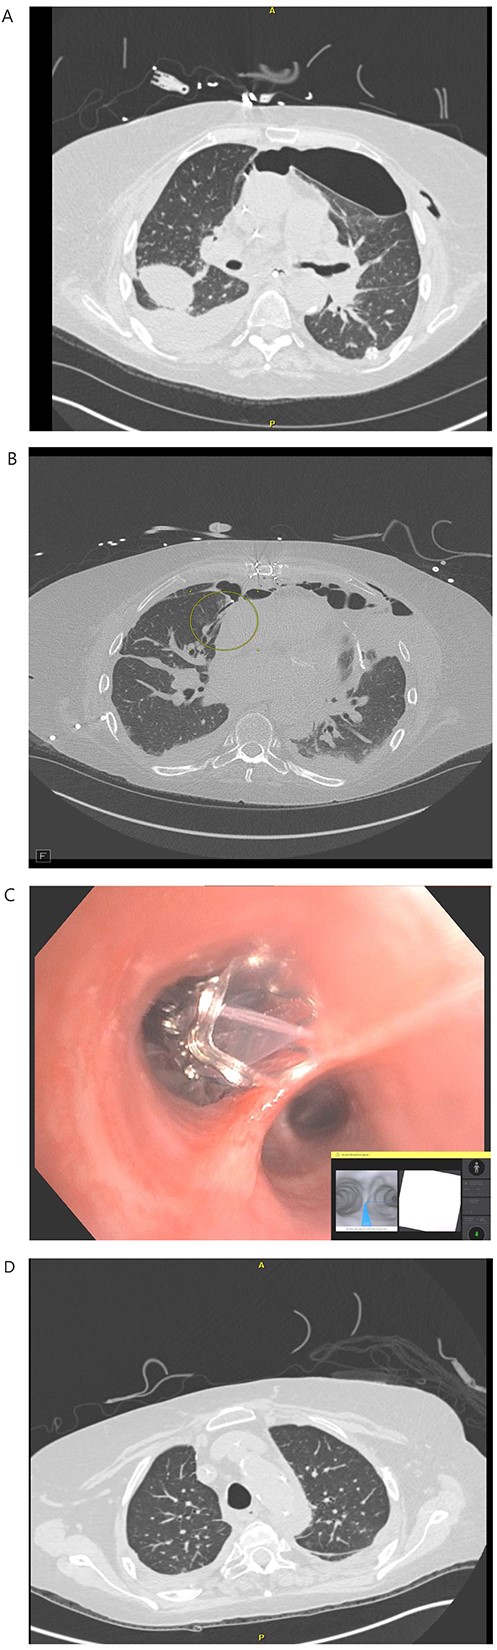

A 71-year-old female with end-stage lung failure underwent a bilateral lung transplant with wedge resection of the right middle lobe and left lingular of donor lungs using Endo-GIA staplers due to oversized lungs. On postoperative day (POD) 21, a BPF was noticed from the right middle lobe at the staple line (Fig. 1B) with persistent bilateral pneumothorax and a loculated right-sided pleural effusion (Fig. 1A) on chest computed tomography (CT) scan that failed conservative treatment with multiple chest tubes. The patient underwent RAB-assisted BPF for closure of BPF on POD 35 using IonTM Endoluminal System. RAB was used to locate and reach the medial lobe bronchial segment of the right middle lobe (Fig. 1C), and a combination of Histoacryl and lipiodol were instilled. The RAB system was then withdrawn, and traditional bronchoscopy was used to deploy the Zephyr® endobronchial valve (Pulmonx, Redwood City, CA) in the medial segment bronchus. An uneventful recovery after the procedure with an improved CT chest (Fig. 1D) was noticed and eventually discharged on POD 57. The EBV was removed on POD 133. At the last follow-up 1-year post transplant, the patient can carry out her daily activities at home without oxygen support.

(A) POD 21 BL pneumothorax and R pleural effusion. (B) POD 31 BPF with medial segment RML with BL pneumothorax and R hydropneumothorax. (C) POD 35 placement of endobronchial valve in medial segment of RML. (D): POD 41 resolution of BPF, pleural effusion and pneumothorax.

RAB has the potential to increase accessibility to peripheral lung lesions. Due to the smaller size of bronchoscopes, electromagnetic or shape sensing technology and the stable instrumentation platform provided by robots, RAB allows the direct visualization of up to the ninth airway segment lesions, including BPF [3]. We chose to use ‘The IonTM Endoluminal System’ because the shape-sensing technology of the video probe allowed live visualization and safe advancing the catheter safely to the proximity of the feeding bronchus.

As the late BPF is challenging to treat, we preferred Histoacryl and lipiodol instead of Progel (BD, Crystal Lake, NJ) to provide more permanent closure. The EBV (which was placed using a conventional bronchoscope) allows air expiration from a treated bronchus but prevents re-inspiration, thus limiting the reopening of the BPF and facilitating closure [4, 5].